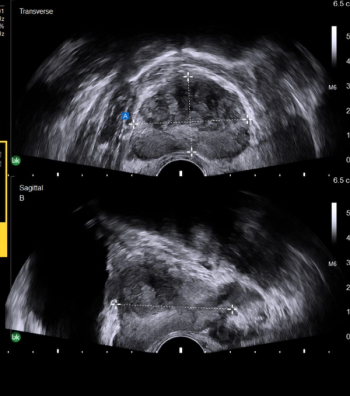

An emerging deep learning algorithm had a lower AUC and sensitivity than urological radiologists for differentiating between small renal masses on computed tomography (CT) scans but had a 21 percent higher sensitivity rate than non-urological radiologists, according to new research.